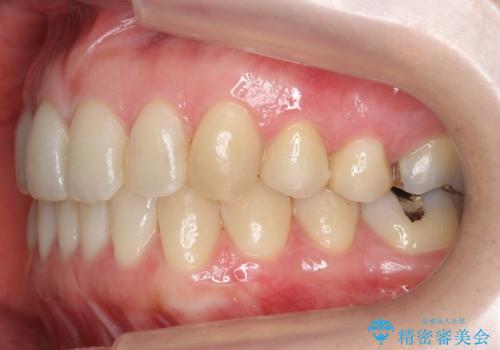

上の前歯が一部引っ込んでいる 下のがたがた マウスピース矯正

- 前歯2本が後ろに引っ込んでいる状態でした。

マウスピースで歯を抜かずに矯正しました。

かみしめがある方は、奥歯のかみ合わせが弱くなることがマウスピース矯正の欠点ですが、装着時間や時間帯を工夫して奥歯もしっかりかんだ状態で矯正終了をしています。

左上4番は、虫歯治療をして、セラミッククラウンで修復しています。